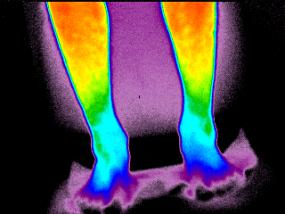

Получены как научные теоретические, так и прикладные результаты. В частности разработана методика согласования параметров матричного приемника излучения с фокусирующей оптической системой [5], предложен метод выявления термоаномальних зон на поверхности тела человека с помощью инфракрасной термографии, проведения анализа и интерпретация полученных данных с учетом кислородного статуса организма (размеры и места локализации термоаномальних зон, температурные градиенты, величина парциального давления кислорода в подкожных тканях). Пример практического применения разработанных методов к диагностированию сосудистых патологий приведен на рис. 2.

а)                                                             б)

Рисунок 2 - Термограммы пациентов с сосудистыми патологиями: а) – варикозно-измененная большая подкожная вена левого бедра; б) – нарушение кровоснабжения дистальных отделов

Показана (рис.2 а) термограмма пациента с варикозно-измененной большой подкожной веной левого бедра. Различие температуры с симметричным участком правого бедра составляет 3,2°С. На рис. 2 б) представлена термограмма нижних конечностей пациента, который жалоб не предъявлял, однако при обследовании которого были выявлены снижения температуры до 28°С (показано стрелками) в сравнении с относительной нормой 32,5°С. После дополнительной осцилометрии и капиляроскопии сосудов стоп выявлена функциональная недостаточность кровоснабжения дистальных отделов.